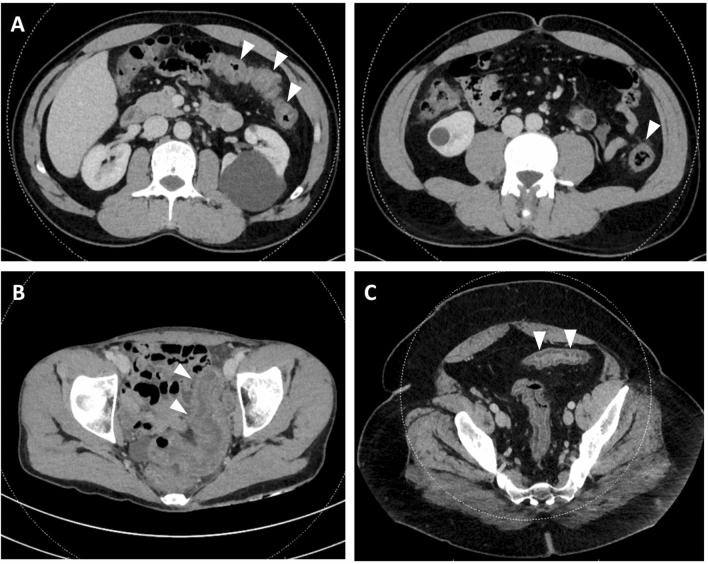

On CT, 29 patients (16.2%) had inflammation of the terminal ileum, 88 (49.2%) of the caecum, 92 (51.4%) of the ascending colon, 79 (44.1%) of the transverse colon, 98 (54.8%) of the descending colon and 92 (51.4%) of the sigmoid colon. Forty-six patients (25.7%) had diffuse inflammation of the colon (pancolitis) (Table 1, Fig. 1). One patient with positive FilmArray GI panel for Entamoeba histolytica had a 5.5 cm abscess of segment VIII of the liver.

Figure 1.

Computed tomography of episode of acute colitis. Arrows indicate areas of colonic inflammation with colonic wall thickening and infiltration of pericolonic fat. (A1 + 2) 46 yo male patient with infectious colitis due to Campylobacter jejuni. (B) 31 yo female patient with undetermined colitis. (C) 42 yo male patient with infectious colitis due to Shigella sonei.